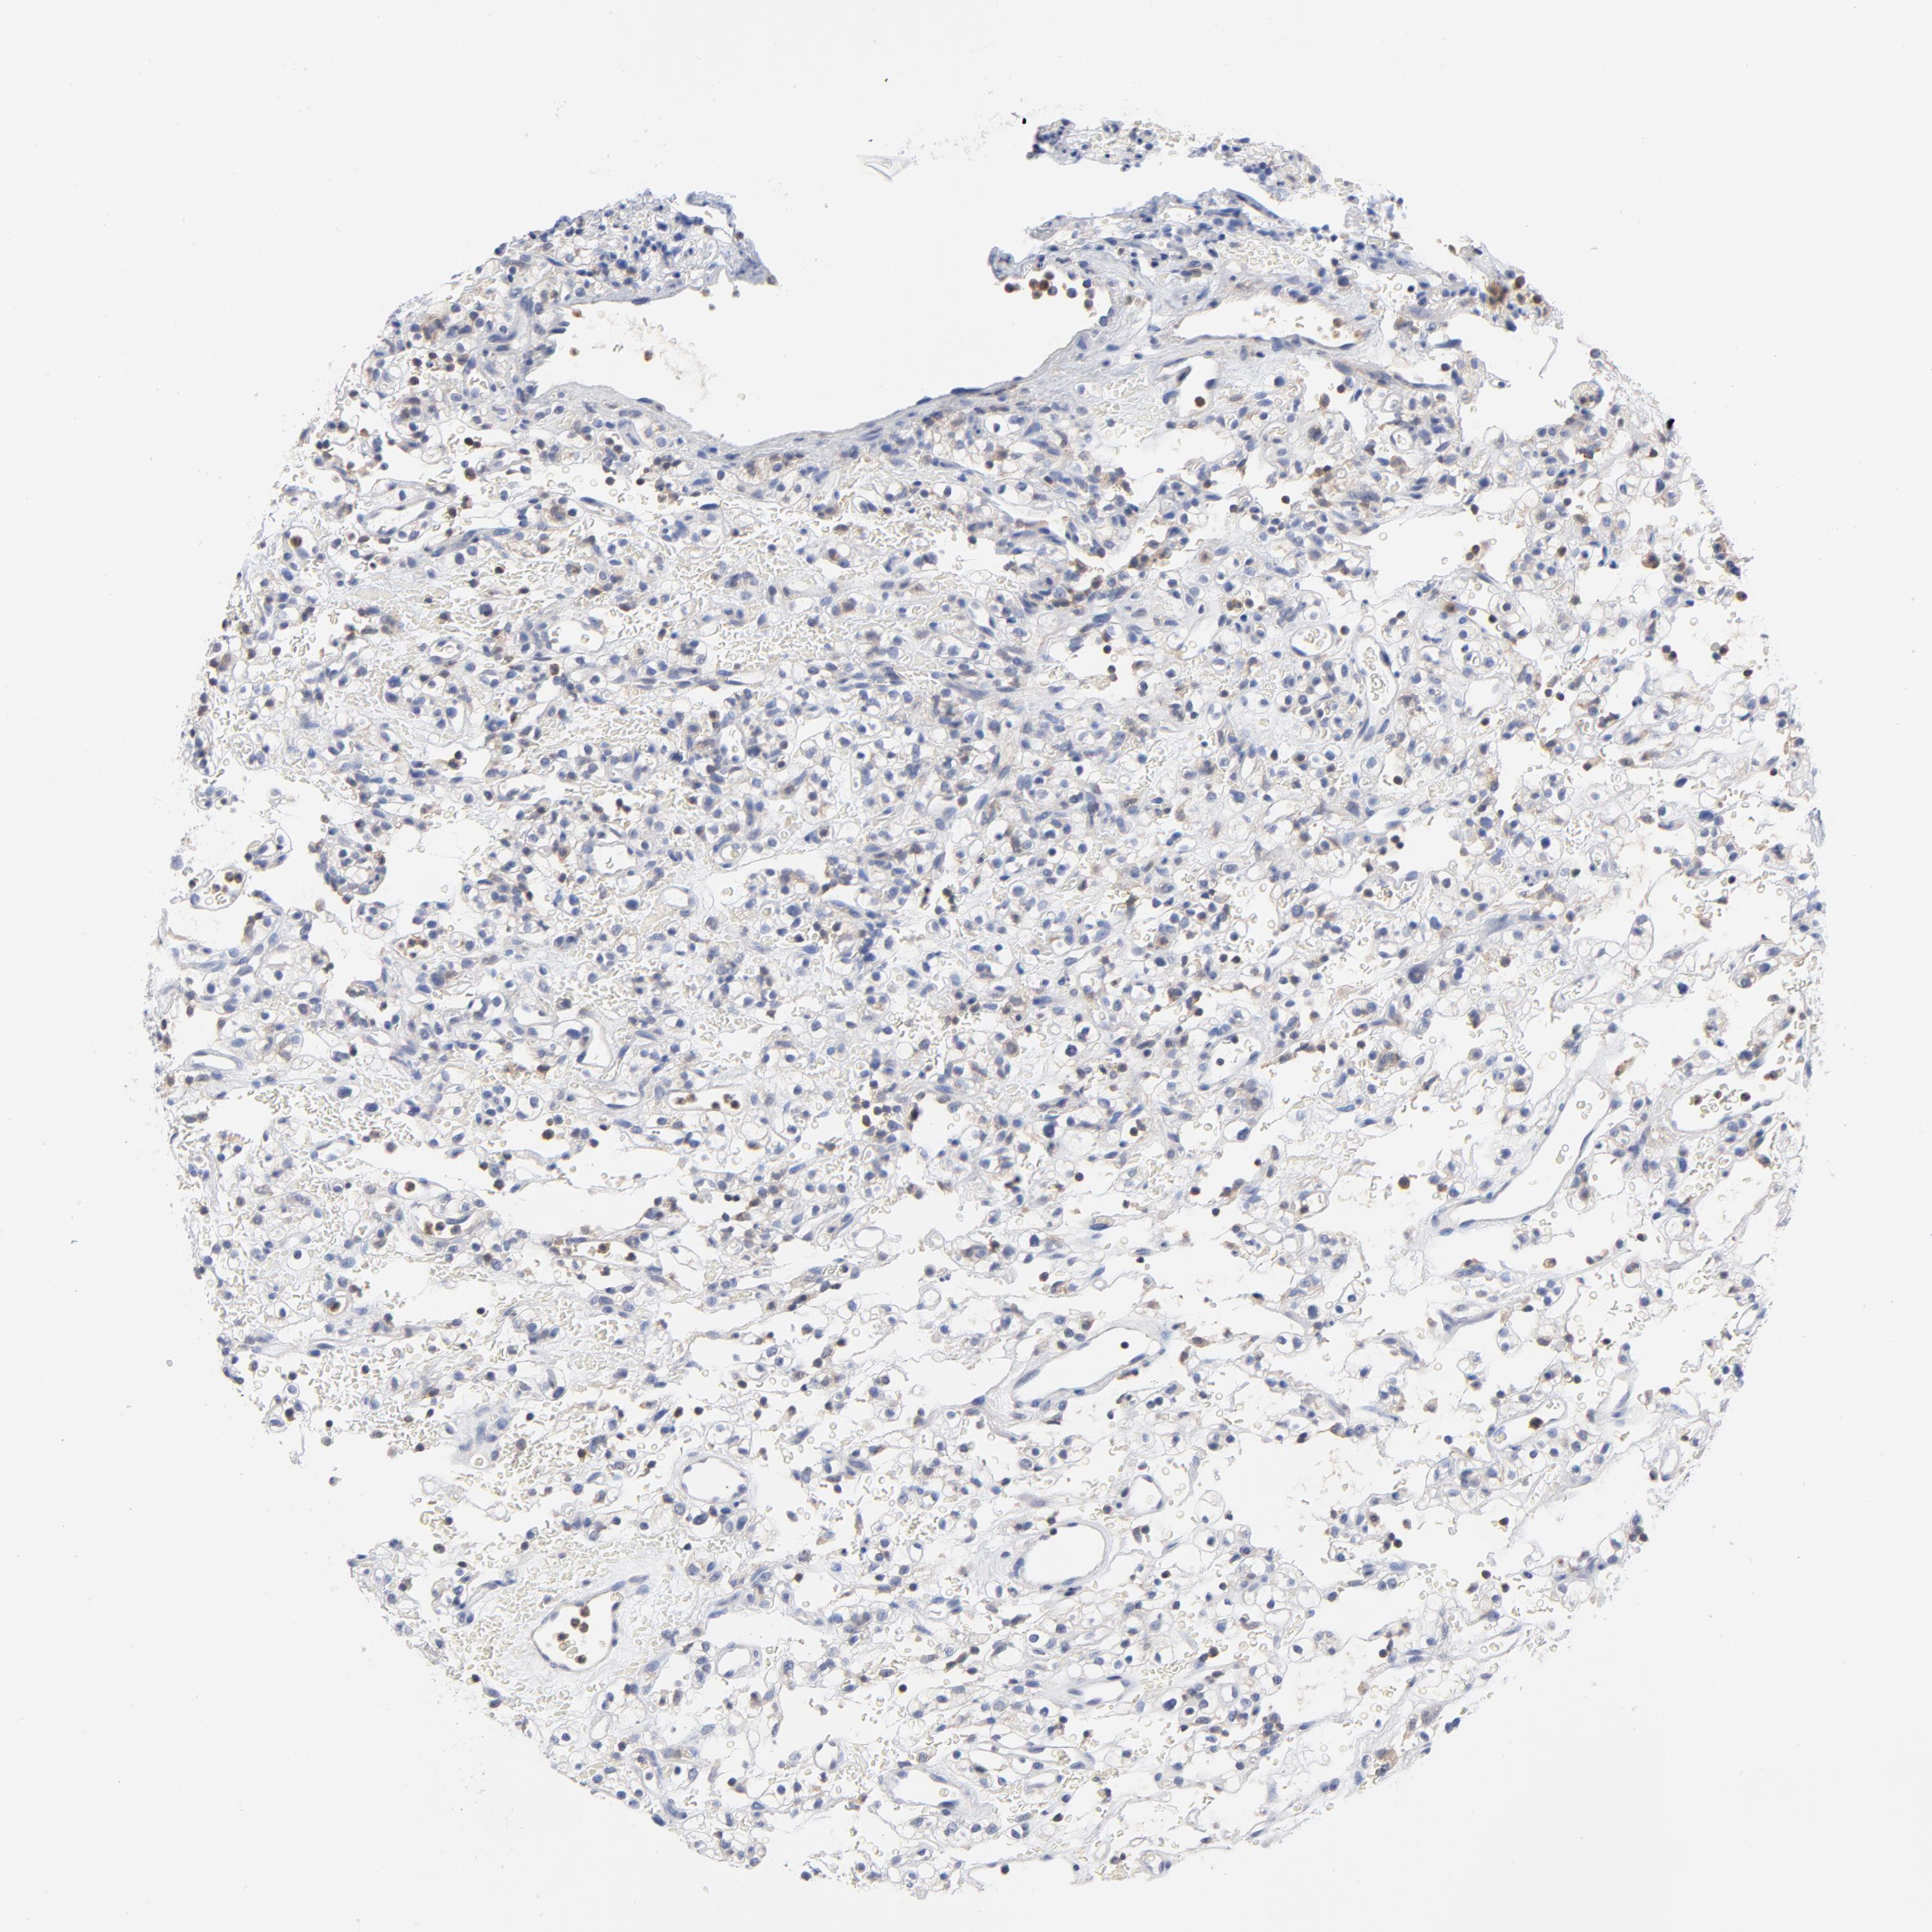

KIDNEY RENAL PAPILLARY CELL CARCINOMA (TCGA) - Interactive survival scatter ploti

The Survival Scatter plot shows the clinical status (i.e. dead or alive) for all individuals in the patient cohort, based on the same data that underlies the corresponding Kaplan-Meier plots. Patients that are alive at last time for follow-up are shown in blue and patients who have died during the study are shown in red.

The x-axis shows the expression levels (FPKM) of the investigated gene in the tumor tissue at the time of diagnosis. The y-axis shows the follow-up time after diagnosis (years). Both axes are complimented with kernel density curves demonstrating the data density over the axes. The top density plot shows the expression levels (FPKM) distribution among dead (red) and alive patients (blue). The right density plot shows the data density of the survived years of dead patients with high and low expression levels respectively, stratified using the cutoff indicated by the vertical dashed line through the Survival Scatter plot. This cutoff is automatically defined based on the FPKM cutoff that minimizes the p-score. The cutoff can be changed by dragging the vertical line or by entering a cutoff value in the square labeled "Current cut-off".

Under the Survival Scatter plot the p-score landscape (black curve; left axis) is shown together with dead median separation (red curve; right axis). Dead median separation is the difference in median mRNA expression between patients who have died with high and low expression, respectively. It is calculated as follows: median FPKM expression of dead patients with high expression - median FPKM expression of dead patients with low expression. This is intended to aid the user in visually exploring custom cutoffs and the associated p-scores and dead median separation.

Individual patient data is displayed and can be filtered by clicking on one or more of the category buttons on the top of the page. Categories describing expression level and patient information include: high, low, alive, dead, female, male and tumor stages. The scale of the x-axis can be toggled between linear and log-scale by clicking on the "x log" button. Mouse-over function shows TCGA ID, patient information and mRNA expression (FPKM) for each patient.

& Survival analysisi

Kaplan-Meier plots summarize results from analysis of correlation between mRNA expression level and patient survival. Patients were divided based on level of expression into one of the two groups "low" (under cut off) or "high" (over cut off). X-axis shows time for survival (years) and y-axis shows the probability of survival, where 1.0 corresponds to 100 percent.

CAB39L is not prognostic in Kidney Renal Papillary Cell Carcinoma (TCGA)

Best expression cut offi

Based on the FPKM value of each gene, patients were classified into two groups and association between prognosis (survival) and gene expression (FPKM) was examined. The best expression cut-off refers the FPKM value that yields maximal difference with regard to survival between the two groups at the lowest log-rank P-value. Best expression cut-off was selected based on survival analysis .

When clicking on this number, the vertical dashed line indicating cut-off, the interactive survival plot, and the Kaplan-Meier curve will be adjusted to show results based on the best expression cut-off.

: 5.09